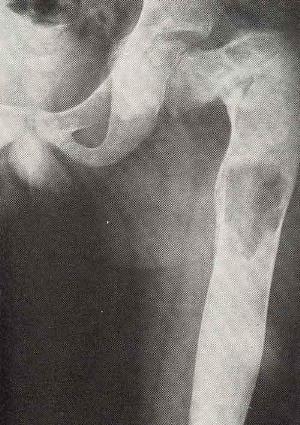

При доброкачественном типе на рентгеновском снимке видны углубления округлой формы на стенках опухоли, злокачественная характеризуется ярко выраженным остеопорозом, а литическая – гомогенным остеопорозом.

Чтобы точно определить этот тип опухоли делают ряд анализов. Рентгеновские снимки обязательны. На них видно истончение кости, которые расползается неравномерно, пораженный кортикальный слой, контуры кости вздуваются булавовидным образом и т.д.